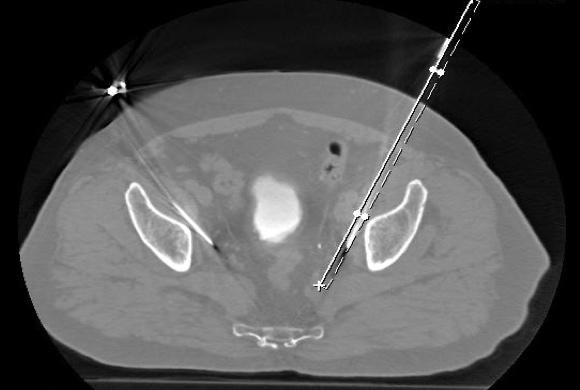

Im VITUS Postata Center nutzen wir dazu ein Infrarot-Guidance System (Cascination, Schweiz), das es ermöglicht, in virtueller Realität den Patienten und seine Organe zu sehen und die für die Ablation benötigten Instrumente millimetergenau in der Metastase zu platzieren. Damit lassen sich auch schwierige Zugänge zu tief im Körper liegende Metastasen navigieren, ohne Gefäße, Nerven oder Organe zu verletzen.

Die Abbildungen zeigten CT und MRT-Scans eines Patienten mit Lymphknotenmetastasen bei einem Prostatakarzinom. Der Patient hatte sich einer Hormonentzugstherapie (ADT Androgen-Deprivations-Therapie) unterzogen, die nicht mehr wirkte. Der PSA-Spiegel war auf 8,65 ng/ml angestiegen. Die Lmyphknotenmetastasen (MRT-Bild rechts oben, Pfeile) sind tief im Becken im Bereich der großen Beckengefäße (Iliakalgefäße) und direkt neben den Ischiasnerven (Nervi ischiadici) lokalisiert. Das Bild rechts oben zeigt die Einbringung der Elektroden in die Lymphknoten im Computertomographen mit Hilfe des infrarotgesteuerten virtual Reality Systems Cascination. Das CT-Bild links unten zeigt die Elektroden in ihrem Verlauf von der Bauchwand bis in die metastasenbefallenen Lymphknoten. Das MRT-Bild rechts unter zeigt das Ergebnis fünf Monate später: Die Lymphknotenmetastasen sind vollständig verschwunden, der PSA-Spiegel sank auf 0,06 ng/ml ab.